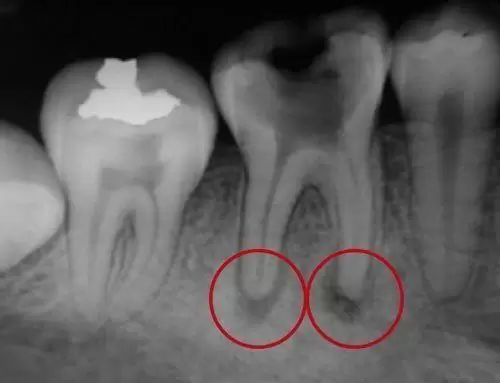

Si, tras la necrosis de la pulpa, no realizamos la endodoncia del diente, la infección de dentro de los conductos puede aflorar alrededor de los ápices radiculares, puntas de las raíces, y afectar al hueso que las rodea. En este caso se empieza a formar una lesión granulomatosa por irritación crónica en el hueso que envuelve la salida de las raíces y que, con el tiempo, puede terminar con la formación de un quiste periodontal.